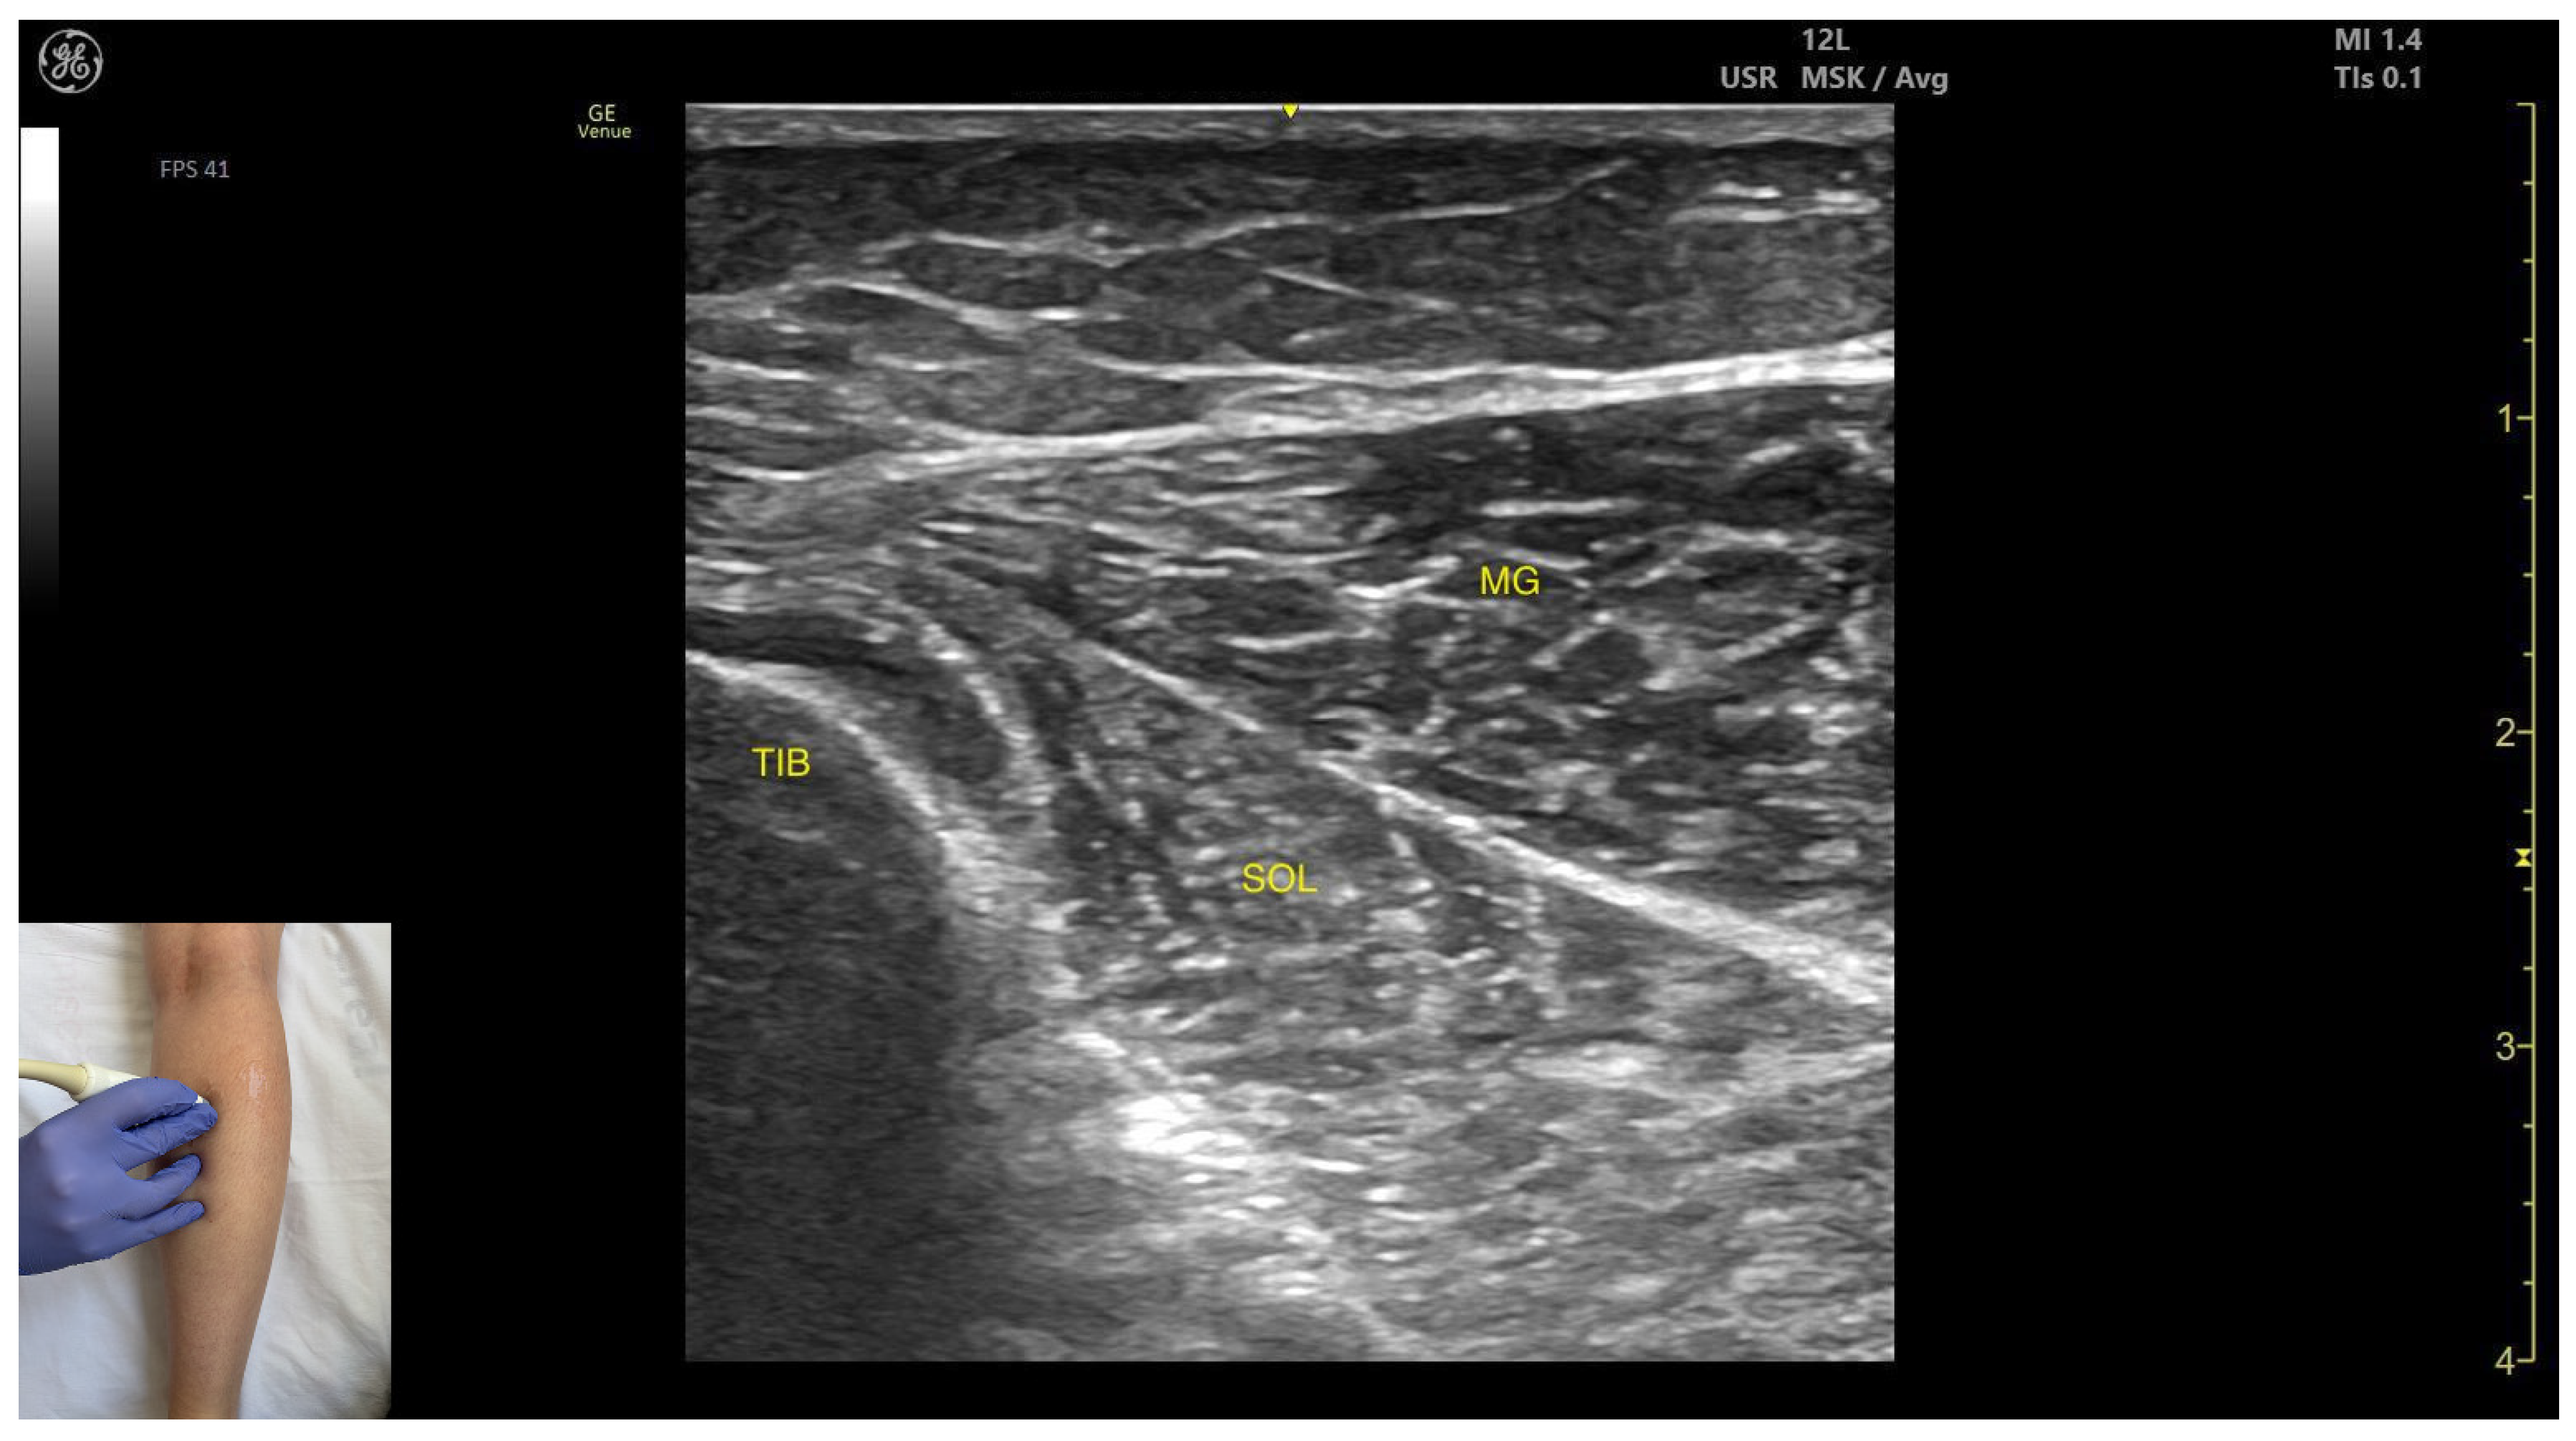

3.1.3. Medial Head of Gastrocnemius (MG)

Ultrasound Identification

Key Ultrasound Landmarks

- Muscle position: It is the most superficial and prominent, and of the largest muscles in the posterior compartment of the leg. The soleus—and if present, the plantaris—is located deep to it.

- Muscle morphology: The medial head of the gastrocnemius is larger and extends more distally than the lateral head of the gastrocnemius.

- External fascia: It presents a well-defined fascia separating it from the subcutaneous plane, soleus, and plantaris muscle/tendon aiding in safe BoNT-A injection.

- Dynamic evaluation: During dynamic evaluation, scanning toward the ankle joint reveals the medial head of the gastrocnemius progressively decreases and eventually disappears while the soleus increases in thickness; further distally, both converge to form the calcaneal (Achilles) tendon, often with the plantaris tendon interposed when present. On lateral scanning the intersection of the medial and lateral gastrocnemius heads is visualized—the medial sural cutaneous nerve typically courses between these heads. The gastrocnemius, spanning both the knee and ankle joints as a biarticular muscle, is evaluated with the knee fully extended to place it under maximal longitudinal tension, thereby accentuating its functional role in ankle plantarflexion. Contraction is visible during plantar flexion of the foot at the ankle joint, as well as during knee flexion.

- Muscle morphology: It appears as a flat muscle in the posterior compartment of the leg.

- Muscle position: At this level, the soleus lies deep to the intersection of the gastrocnemius heads, within which the medial sural cutaneous nerve courses.

- External fascia: A pronounced fascia separates it from the subcutaneous plane, gastrocnemius muscles, and the plantaris muscle/tendon (if present), which is relevant during BoNT-A injection.

- Dynamic evaluation: During dynamic evaluation, scanning laterally reveals enlargement of the lateral gastrocnemius head, and deep to the soleus, the neurovascular bundle emerges, comprising the posterior tibial artery, the two posterior tibial veins, and the posterior tibial nerve. Medial scanning highlights enlargement of the medial head of the gastrocnemius (MG), while the neurovascular bundle maintains its anatomical course. The soleus, a monoarticular muscle acting exclusively at the ankle joint, is optimally assessed with the knee flexed; this positioning diminishes gastrocnemius involvement, allowing for isolated evaluation of soleus contractile activity via EMG or dynamic ultrasound imaging. Muscle contraction is visible during plantar flexion maneuvers of the foot at the ankle joint.